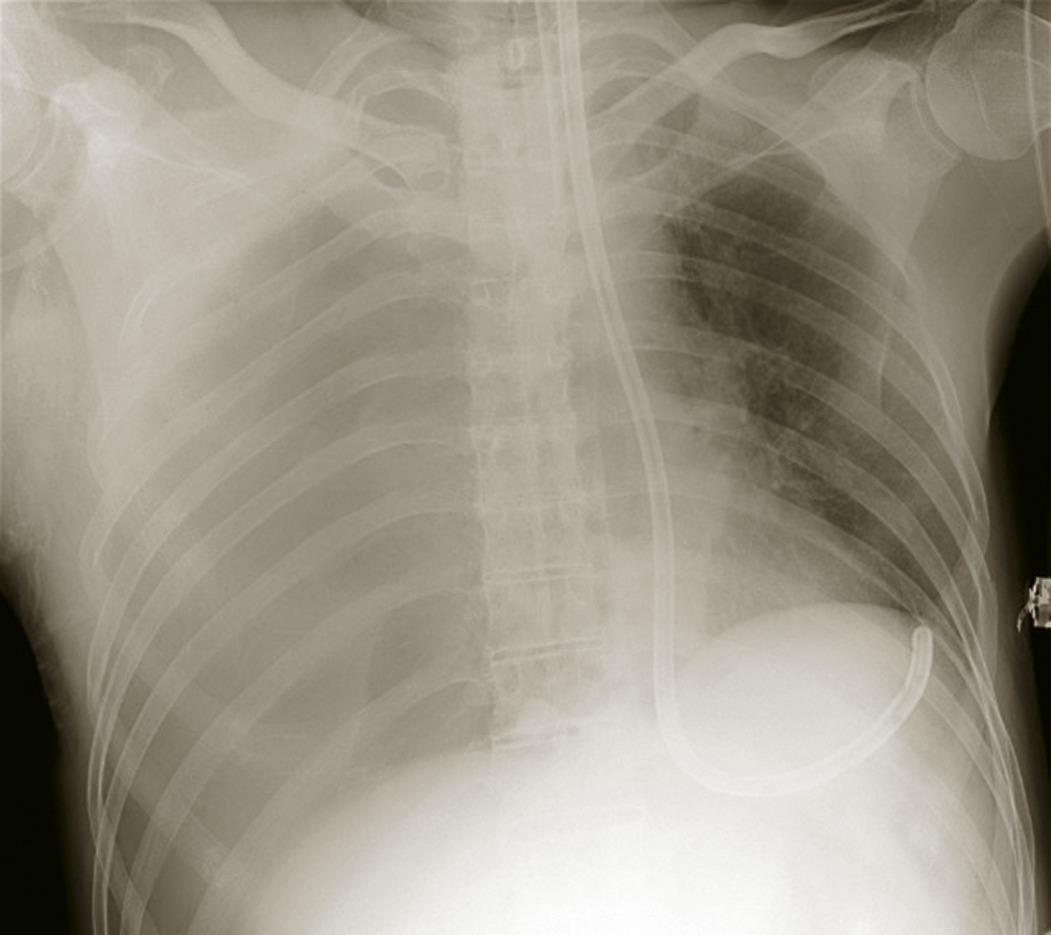

• une radiographie thoracique de face (fig. 2) pour confirmer un pneumothorax compressif ;

Pneumothorax (fig. 4)

Il est secondaire à une plaie pariétale, du parenchyme pulmonaire ou de l’arbre trachéobronchique. Il justifie un drainage s’il est complet ou mal toléré. Il peut être compressif si l’air qui entre dans la cavité pleurale y reste trappé, aboutissant à une compression des structures médiastinales et de l’hémithorax controlatéral. Il doit alors être drainé en urgence ou exsufflé par voie médio-claviculaire au 2e espace intercostal ou sur la ligne axillaire antérieure au 4e espace intercostal.